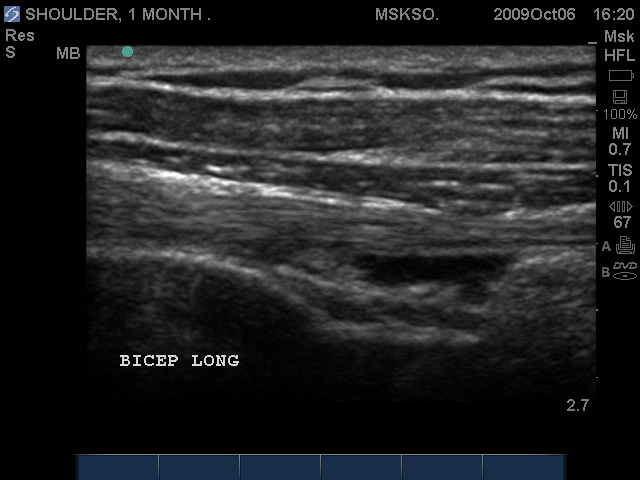

Long axis Bicep tendon with synovial fluid at level of surgical neck